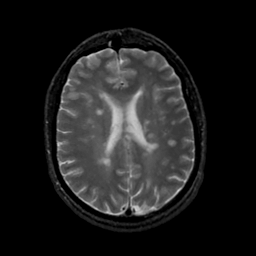

MR Study #18, July 21, 1991 -- Slice #31

[Home][Help][Clinical][Tour 1][Tour 2] Slice 31